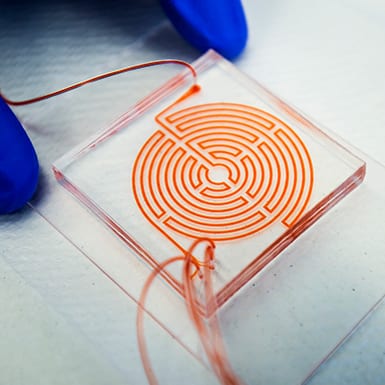

Is lung cancer treatment working? This chip can tell from a blood draw

By trapping and concentrating tiny numbers of cancer cells from blood samples, the device can identify whether a treatment is working at the four-week mark.

Lab-on-a-chip offers faster means of identifying best plasma donors in COVID fight

University of Michigan collaboration with Hackensack Meridian CDI offers new pathway to identify antibodies.